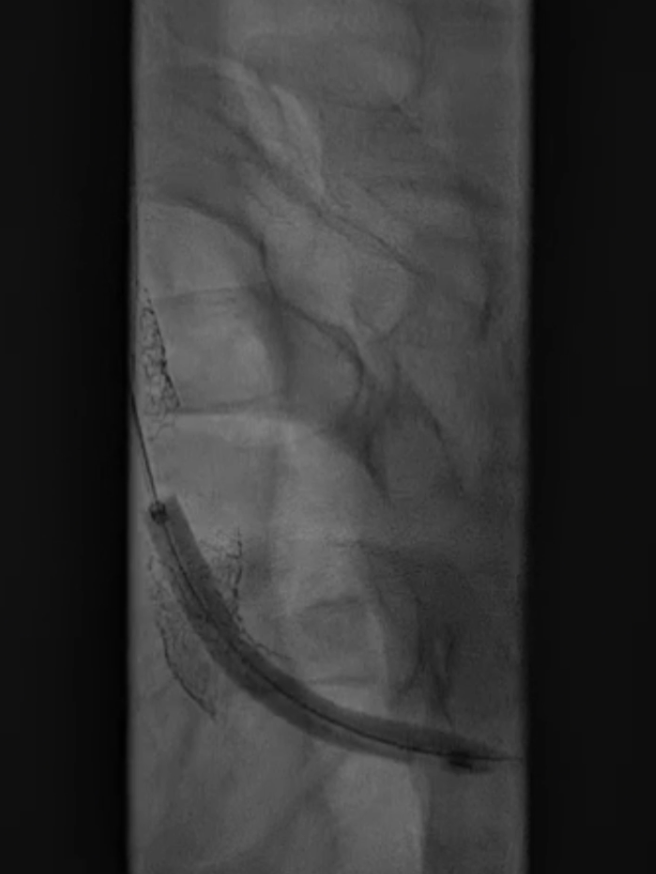

收尾操作:再次以球囊带鞘方式跟进长鞘至支架远端,回收保护伞;最终造影显示支架内血流通畅,右锁骨下动脉、右颈动脉、椎动脉显影良好,椎动脉血流速度较术前明显改善。

长鞘上行困难

回收保护伞

再次球囊带鞘

更进至支架远端

造影支架内通畅

右锁骨下动脉 右侧颈动脉

血流通畅椎动脉显影好